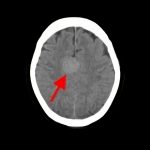

断層撮影

手術前2